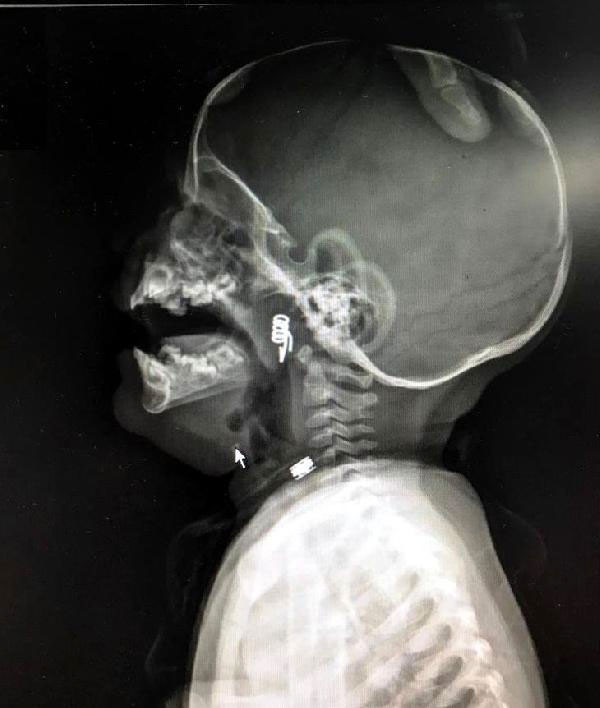

NEVŞEHİR'de inanılması güç bir olay yaşandı. 1 yaşındaki erkek bebek Ö.Y. önüne konulan çamaşır mandalıyla oynarken mandal dağıldı. Minik bebek de mandalın metal yayını hemen ağzına attı. Bebeğin ani tepki verip yutkunması sonrası metal yay, çocuğun boğazına kaçtı. Hastanede çekilen röntgende yayın yeri tespit edildi. Bebeğin nefes borusuna saplanan yay başarılı bir operasyonla çıkarıldı.

Nevşehir Devlet Hastanesi Acil Polikliniği'ne getirilen bebeği, Acil Nöbetçi doktoru Mustafa Alpaslan muayene ederek gerekli tetkikleri yaptı. Çekilen röntgen filmlerinde mandal yayının lokalizasyonu ve durumu belirlendi. Daha sonra, KBB Uzmanı Op. Dr. Ahmet Cevatzade tarafından yapılan başarılı ameliyat sonucunda bebeğin genzine saplanan mandal yayı çıkartıldı.